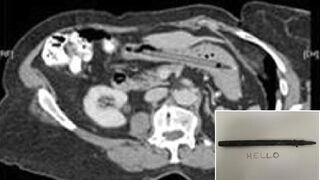

Pen Recovered From Woman's Stomach 25 Years Later Still Writes